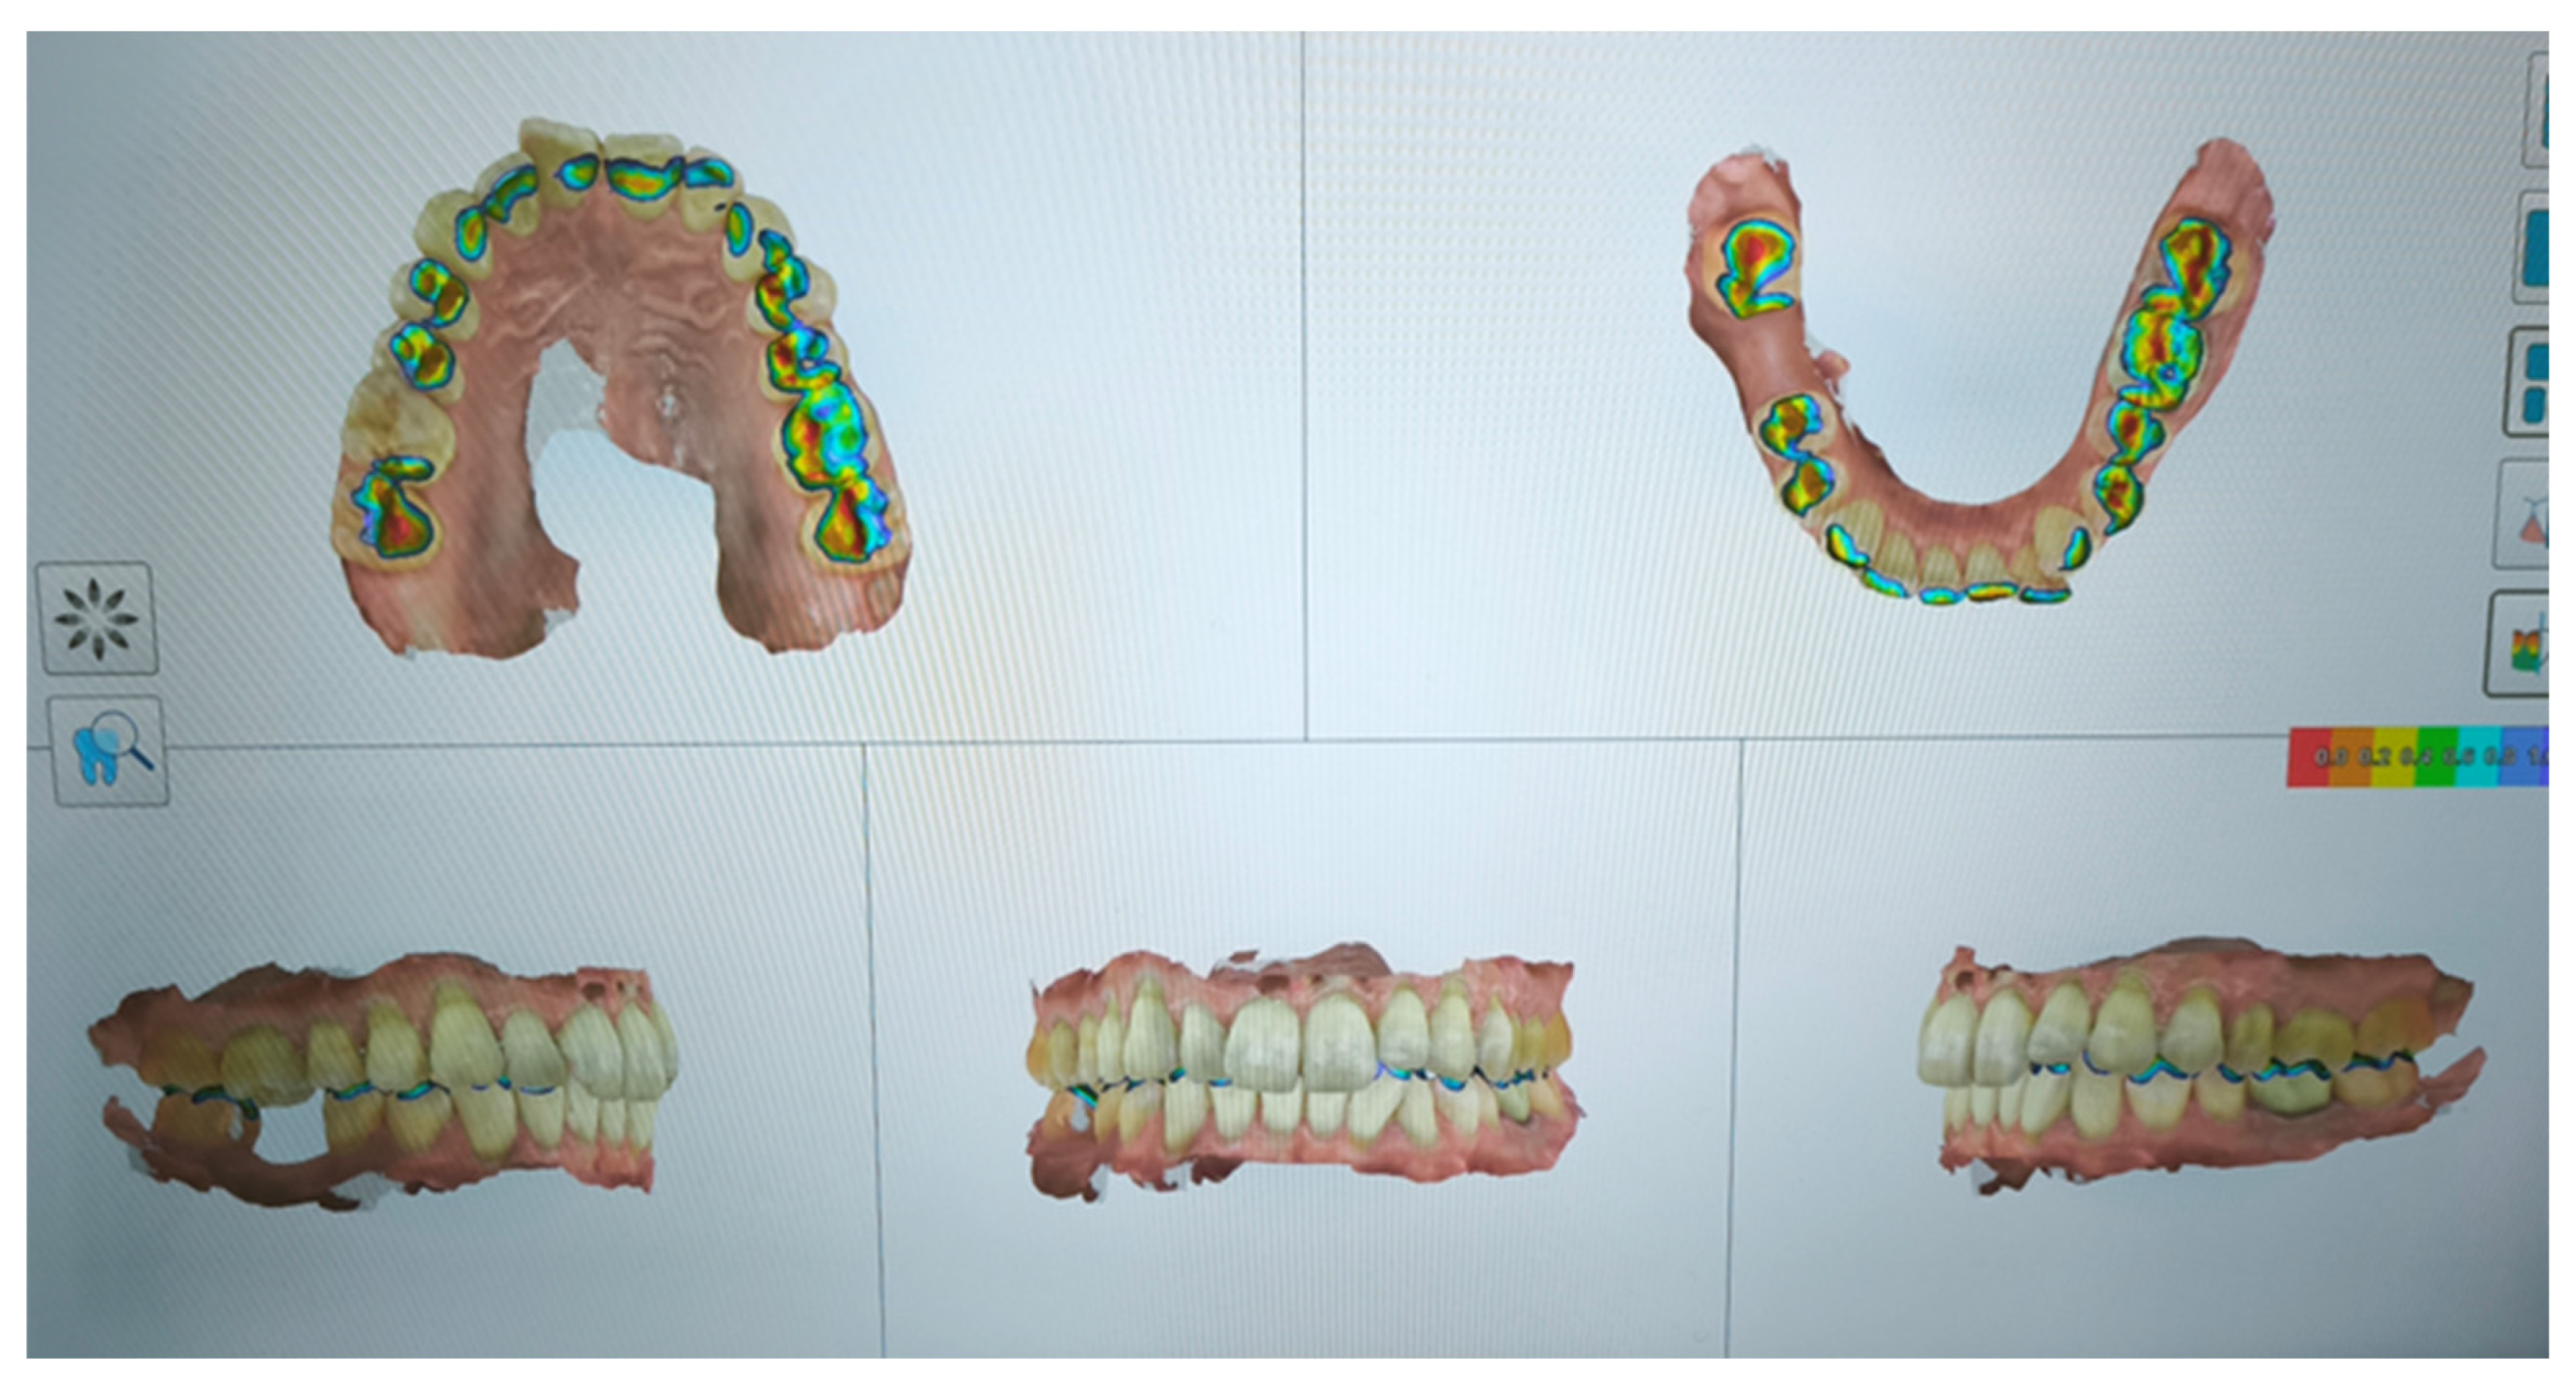

2.3. Diagnosis and Treatment Planning

2.3.1. Gnathological Therapy

2.3.2. Orthodontic Therapy

| ORTHODONTIC THERAPY | use of 30 pairs of clear aligners (15 days each couples) |

| after 1 year | refinement with 15 pairs of clears aligners (use 15 days each couples) |

| after 8 months | Retainers + CBCT (t1) + final photos |